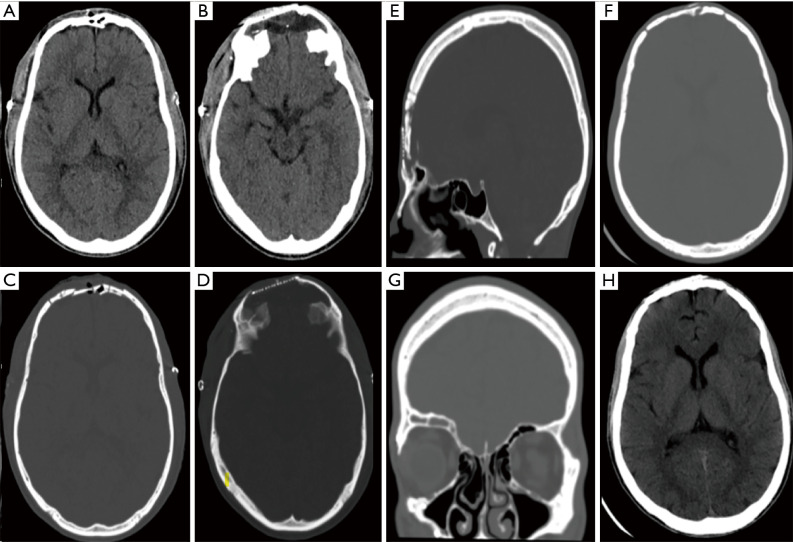

Case description: We present a 21-year-old male who was involved in an MVA with an unknown mechanism and was brought by ambulance to our emergency department at Dammam Medical Complex. Initially, the patient was vitally stable, conscious, alert, and oriented. He had multiple scalp lacerations, including a mid-forehead open wound laceration with bone fragments and some brain tissue protruding out of the lacerated wound defect. After clinical deterioration, the patient underwent an urgent surgical exploration and elevation of skull fracture along with primary skull reconstruction. The mid-forehead wound defect was repaired in collaboration with the plastic surgery team.

Conclusions: Although a depressed frontal skull fracture involving both the outer and inner tables of the frontal sinus needs to be addressed on a case-by-case basis, cranialization of the inner table is preferred. Titanium mesh is a satisfactory alternative in case of inapplicable use of the patient's own bone fragments and chips. Collaborating with the plastic surgery team when dealing with complex mid-forehead wounds is also advisable to ensure optimal cosmetic outcomes. It is advisable to use anti-seizure medications (ASMs) prophylactically to prevent early, but not late, post-traumatic seizures (PTSs). A short course of broad-spectrum antibiotics is recommended in cases of open (compound) depressed fractures.